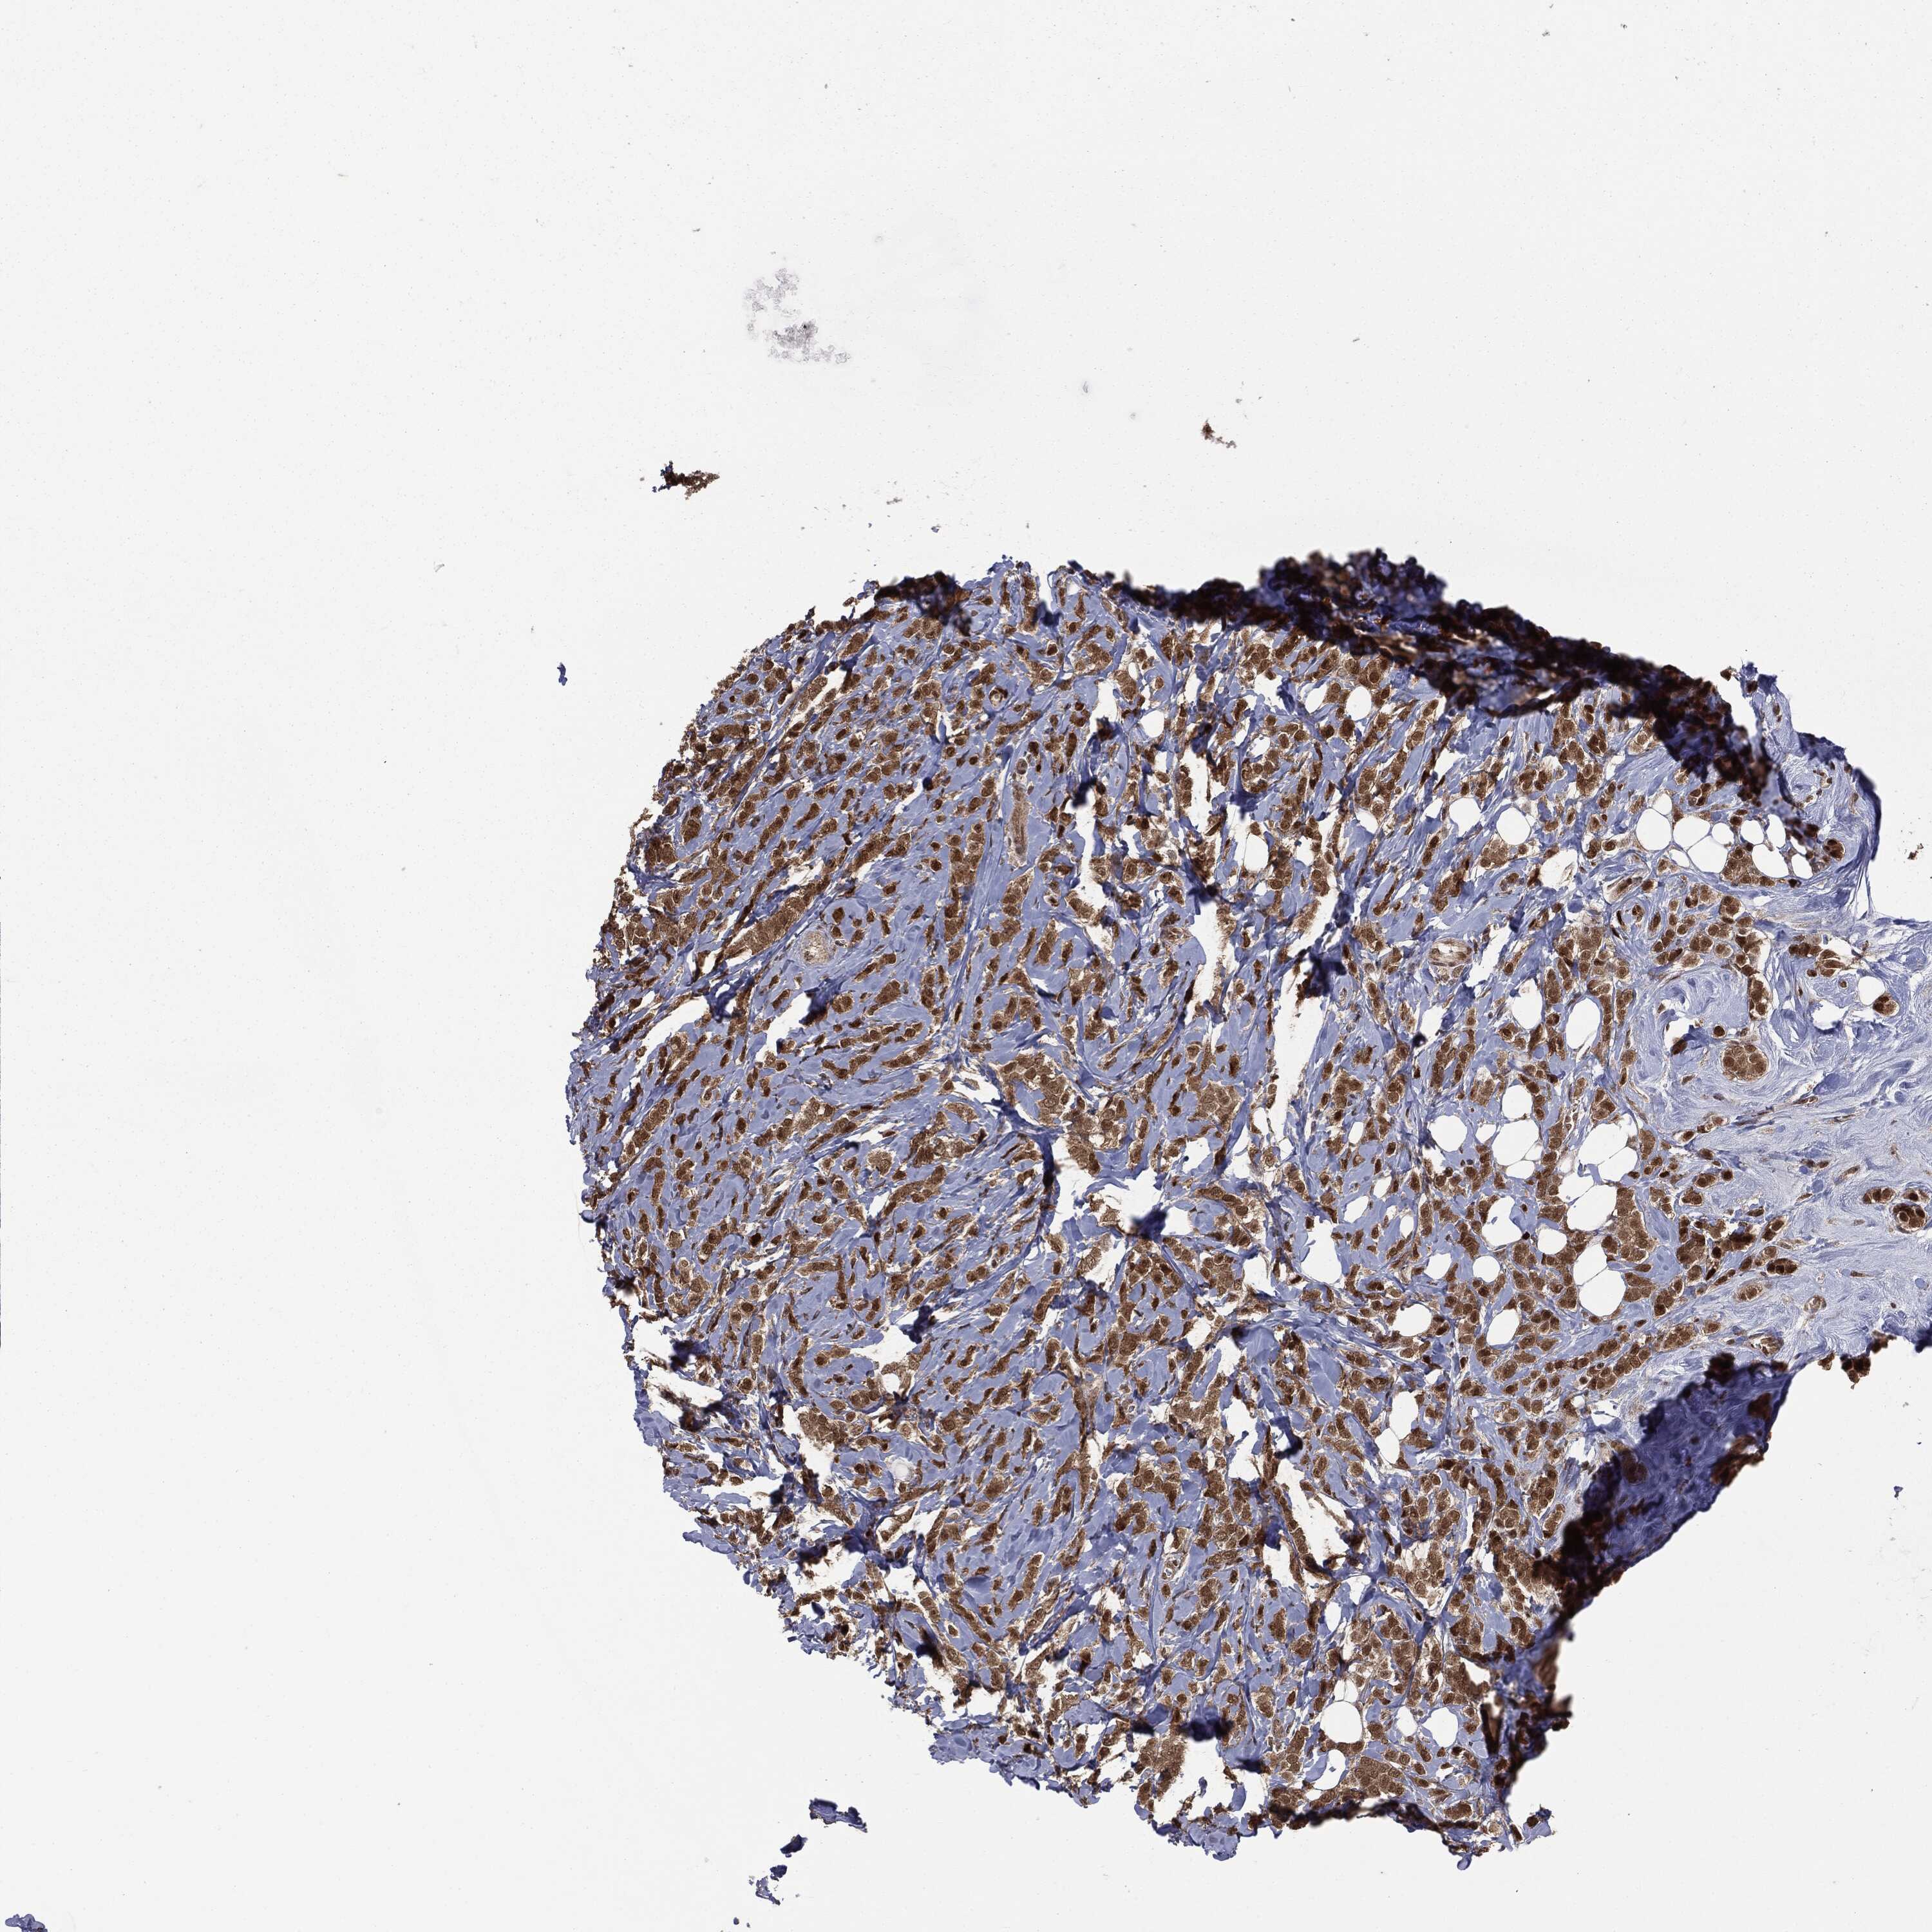

BRCA TCGA BRCA VALIDATION PROTEIN EXPRESSION

ANTIBODIES

AND

VALIDATION